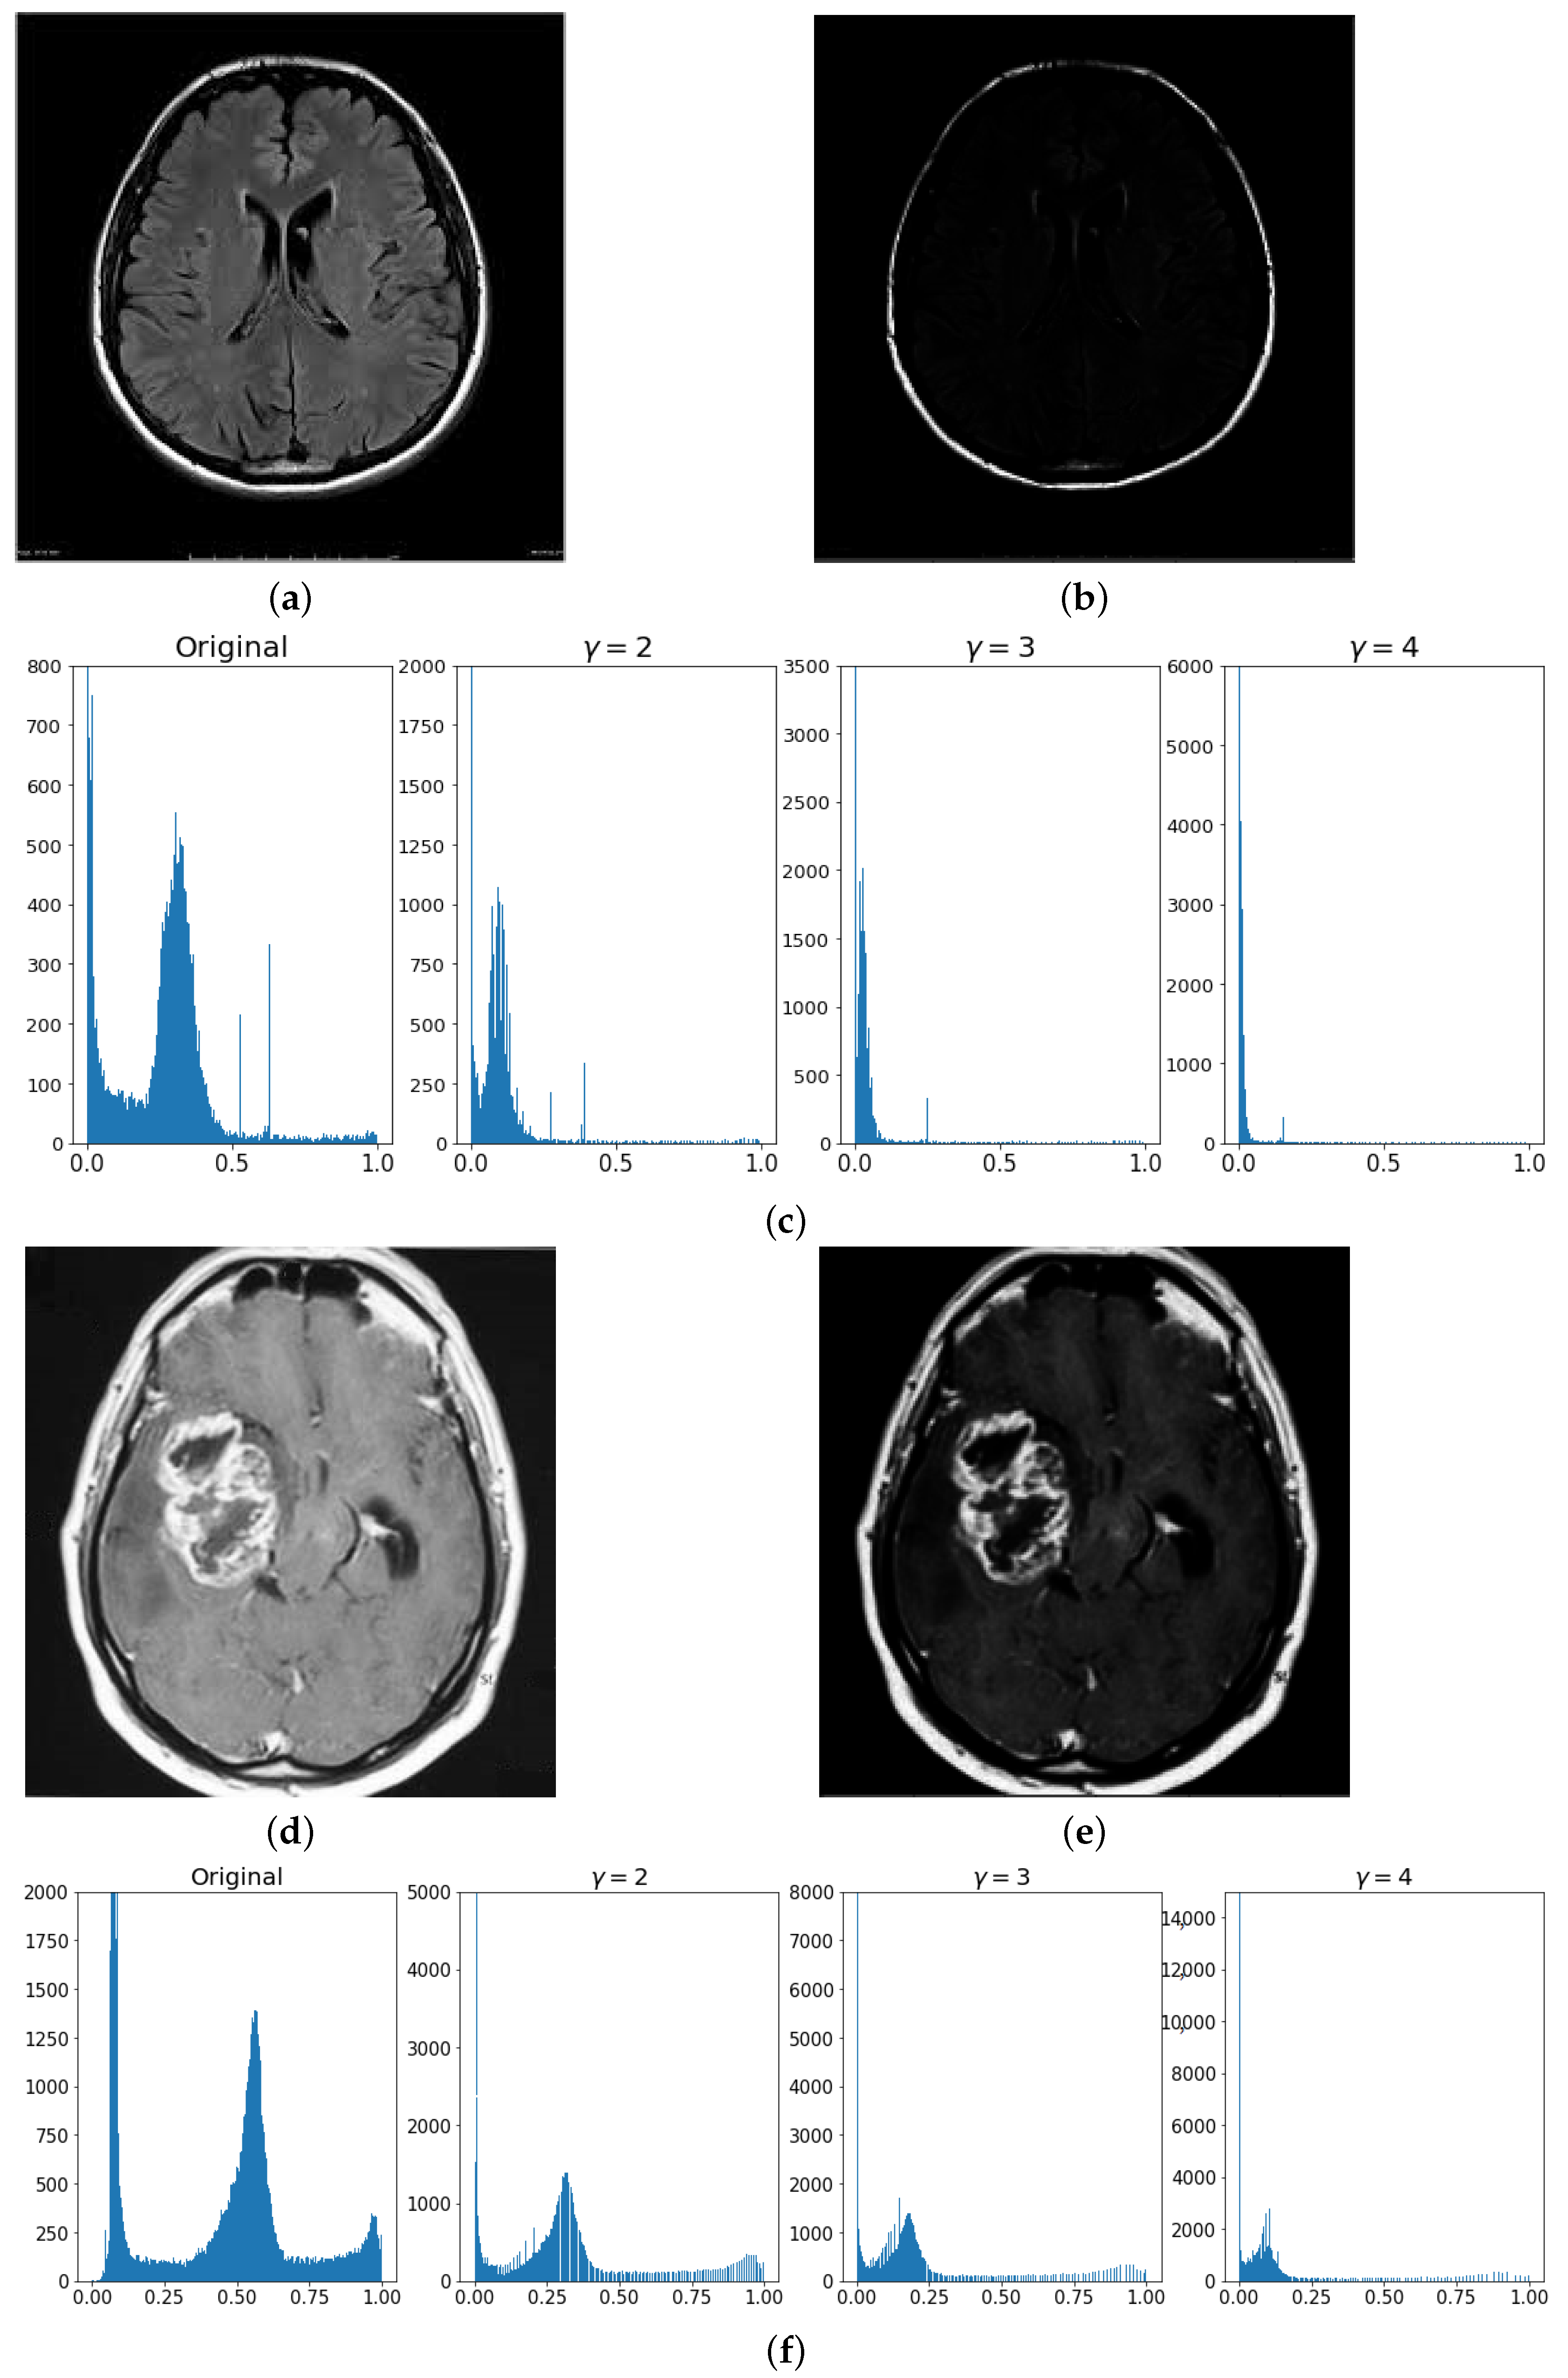

3.1. Pre-Processing

3.3. Correction